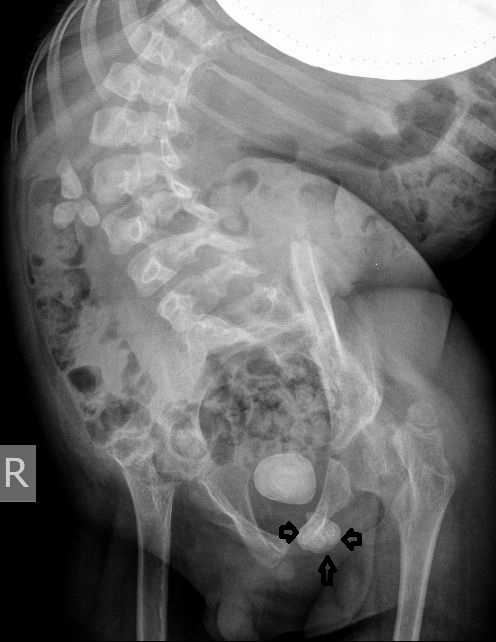

Для того, чтобы продемонстрировать степень ортопедических проблем и облегчить задание (или усложнить :) ) добавляю обзорную рентгенограмму брюшной полости

Поскольку откликов нет, добавляю экскреторные урограммы этого же пациента

Нейрогенный мочевой пузырь (?), МКБ, конкремент мочевого пузыря, двухсторонний мегауретер, конкремент правой почки.

Всё верно, только что вот это ?

И что законтрастировалось на экскреторных урограммах около мочевого пузыря?

Если честно, и я изначально не совсем понял, где находится конкремент (а это конечно же конкремент), локализованный на урограммах. При первичном исследовании на УЗИ его я не видел (либо он спрятался за тенью конкремента мочевого пузыря, либо я обрадовался редкой находке конкремента такого размера в мочевом пузыре - 2.5 см, и не посмотрел что ниже). Тем не менее при ретроспективном анализе архивированных сонограмм, как мне кажется, он попал в один из сканов, м.б. не совсем чётко.

И всё -же, где конкремент :?:

Возможно, в дивертикуле либо в нижней трети мочеточника..

Верификация:

Выдержка из протокола операции- "...вскрыт мочевой пузырь, обнаружен камень 4 х 3х 2.5 см, плотный, удалён. При дальнейшей ревизии мочевого пузыря обнаружен вколоченный камень в шейке мочевого пузыря и в уретре, удалён камень 2 х 1.5 х 1.5 см. При осмотре устья левого мочеточника - последний зияет, мочеточник расширен до 1 см, учитывая расширение мочеточника, проведена антирефлюксная пластика по Грегуару..."